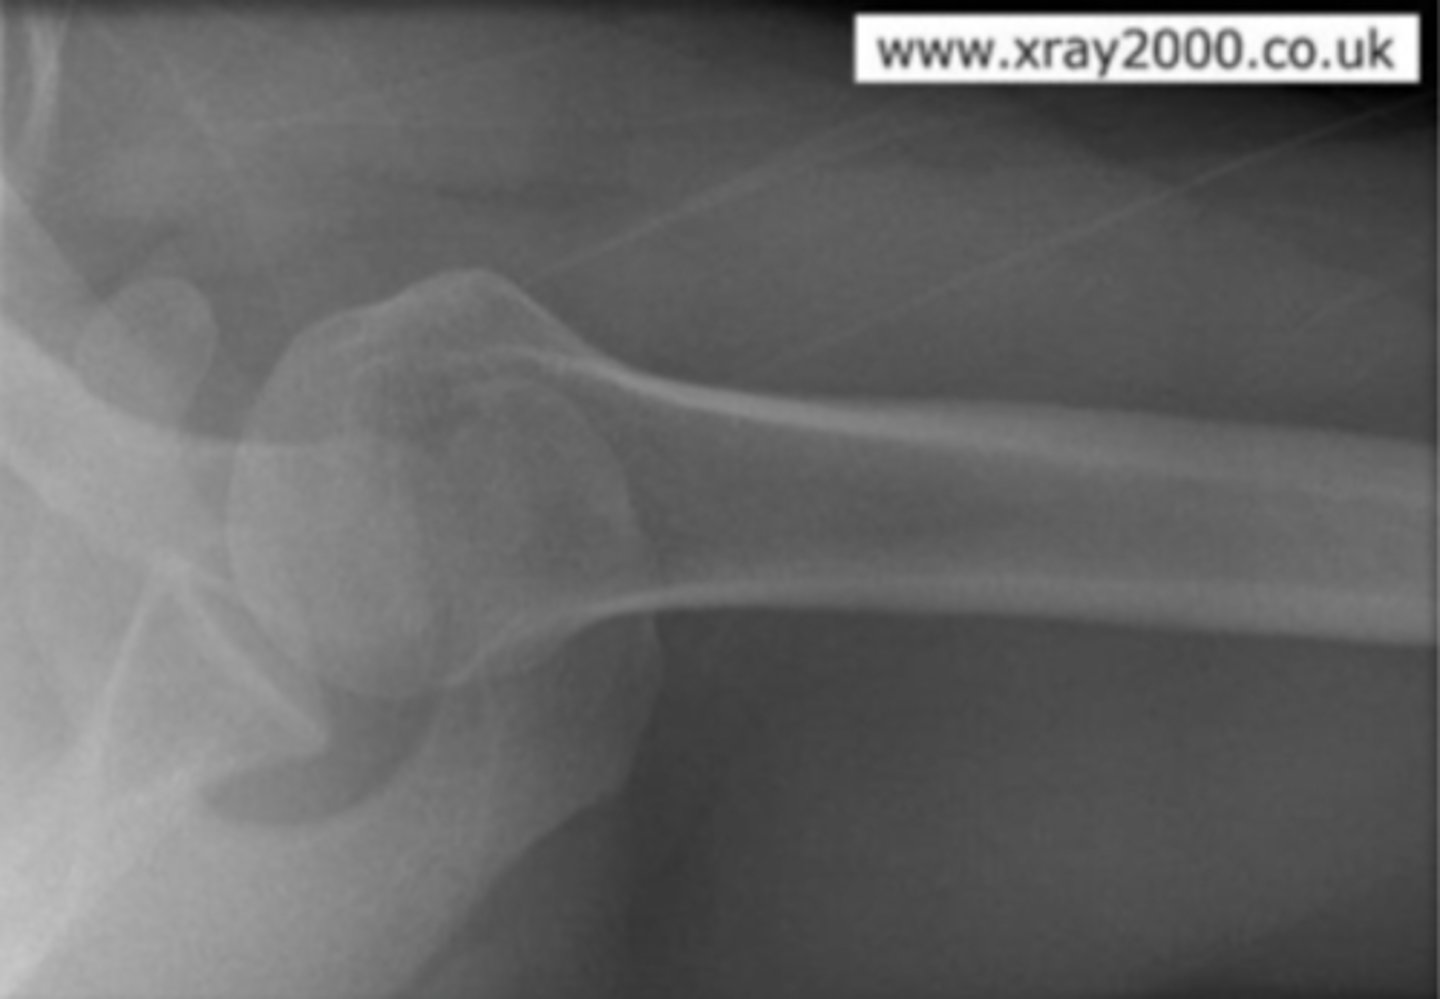

Hill Sachs lesion

What is the issue?